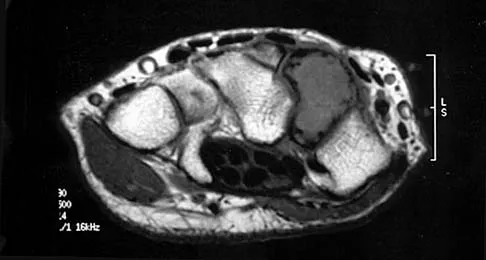

A 30-year-old man has had intermittent swelling of his right ankle for the past 6 months. He denies any history of trauma. Radiographs reveal osteolytic changes on both sides of the joint. An axial CT scan and a T2-weighted MRI scan are shown in Figures 40a and 40b. He undergoes surgical excision. An intraoperative photograph and a biopsy specimen are shown in Figures 40c and 40d. What is the most likely diagnosis?